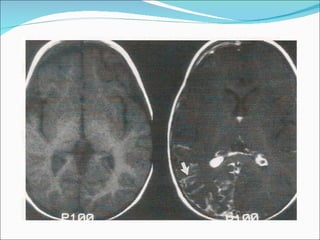

1) O documento descreve o Síndrome de Sturge-Weber, uma condição neurocutânea não hereditária caracterizada por nevo facial e convulsões. 2) O Angioma Cutâneo de Sturge-Weber aparece na área de inervação do trigêmeo, enquanto o Angioma Leptomeningeal aparece nos sulcos corticais parietais e occipitais. 3) Os achados de imagem incluem realce no espaço subaracnóideo e hipersinal na substância branca adjac